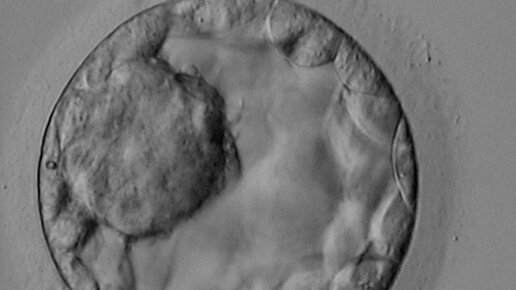

Содержание митохондриальной ДНК (мтДНК) Предполагается, что содержание мтДНК в эмбрионах человека может быть индикатором жизнеспособности эмбриона и его потенциала к имплантации. В нескольких исследованиях были получены противоречивые результаты по содержанию мтДНК в соответствии с сутками развития эмбриона, его качеством, возрастом матери, способностью к имплантации. В связи с новизной данной темы, оценка мтДНК не включена ни в клинические рекомендации, ни в обследование. В самом недавнем исследовании...